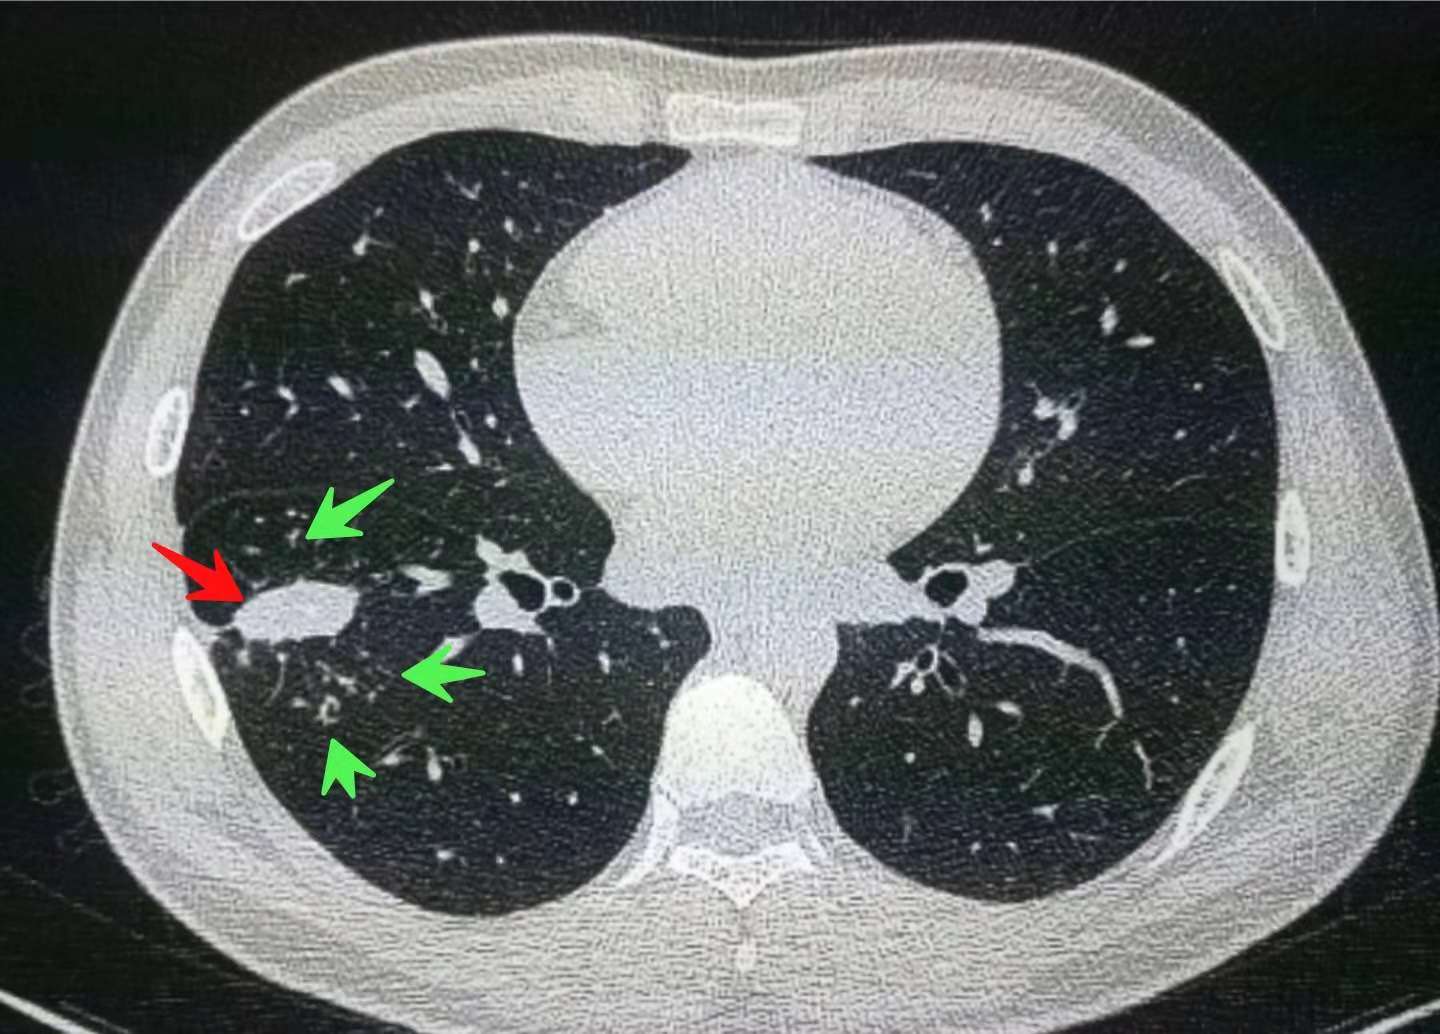

其实我们深入分析,病灶周围可见多发斑点状状,小树芽状高密度影(绿色箭头所示),这个我们称为“卫星灶”,形态多样,像一些小卫星环绕着中央的大病灶,是肺结核(结核球)的常见征象,并且常常代表病变处于活动期,需要积极治疗!

通过密度测量,我们还发现病灶内部有多发钙化斑点,更加支持肺结核的诊断。